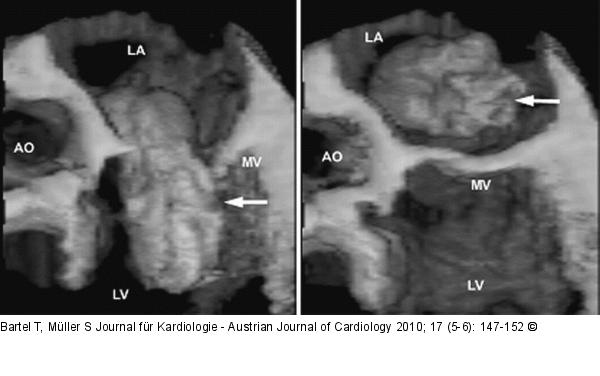

Abbildung 4: Myxom Papilläres, gelatinöses Myxom (links: Diastole, rechts: Systole) mit hoher Embolisationswahrscheinlichkeit prolabiert diastolisch in den linken Ventrikel. Ao: Aorta; LA: linker Vorhof; LV: linker Ventrikel; MV: Mitralklappe. |